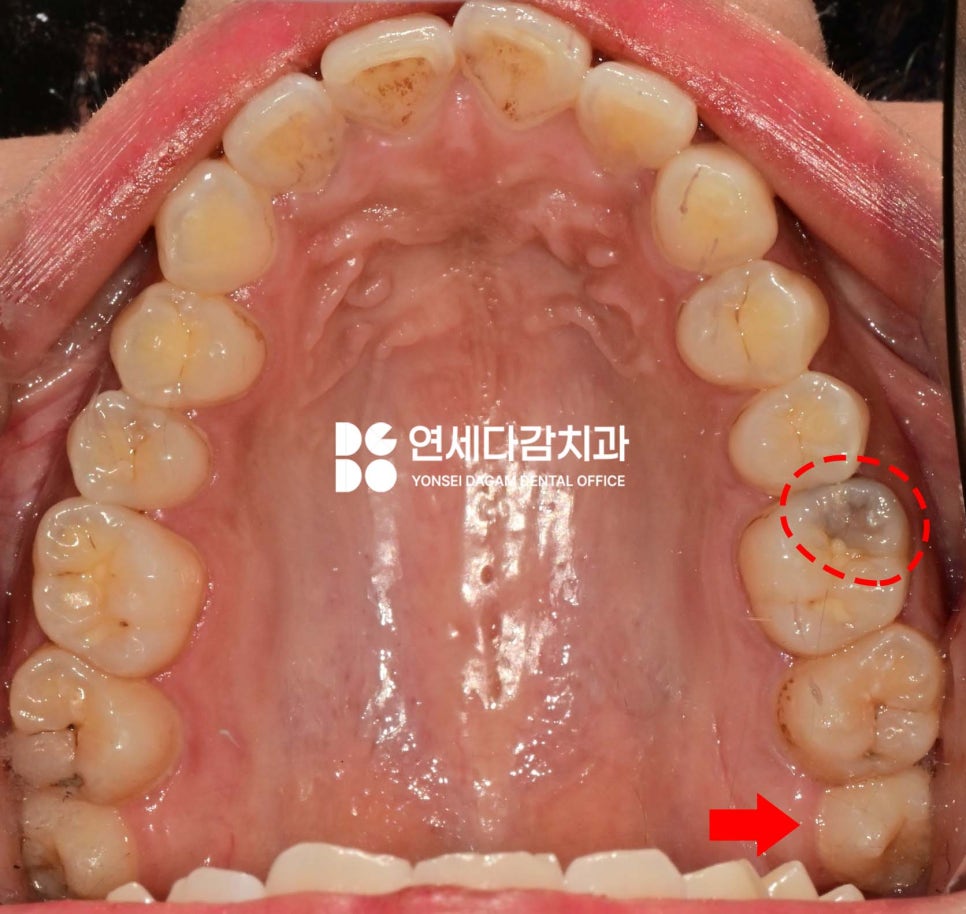

구강 검사 결과,

아래 매복 사랑니 주변으로

특히 심한 부종이 관찰되었으며,

해당 부위를 촉진했을 때

고름이 나오기도 했습니다.

이는 감염(지치주위염)이 진행 중임을

나타내는 명백한 징후였습니다.

추가로 위쪽 사랑니 부위에도

음식물이 자주 끼고,

평소 위생관리에 어려움을 겪고 있었습니다.

또한 어금니 중 하나는

심한 인접면 충치가 발견되었습니다.

충치가 치수(신경)에 도달한 것은 아니었으나,

범위가 넓게 퍼져있어

그 부위를 모두 제거하면 치관의

상당 부분이 사라지게 됩니다.

따라서 레진 코어를 통해

치관 구조를 재건한 뒤 크라운을 씌워

보호하는 것이 좋다고 판단되었습니다.